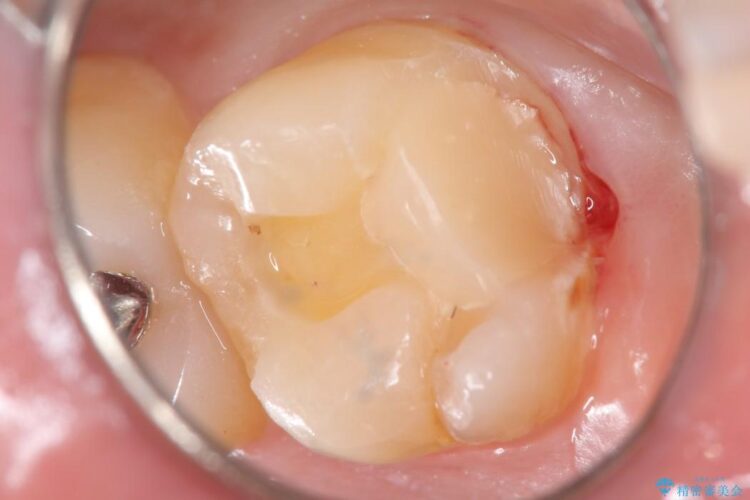

上顎左の一番奥の歯が深い虫歯になって脆くなり、更にその状態に強く噛みしめたわけではない通常の咬合力が加わったことで歯が欠けてしまっていました。

今回は一番奥の歯という位置と、噛み合わせ、清掃状態を加味して適合の高く長持ちするゴールドインレーにて治療することとしました。